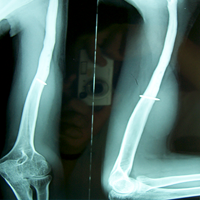

Case:7 GCT Humerus

Spine Surgeon Best In Rajasthan

Pre-Op

Sports Injuries Doctor

3 Years follow-up

Orthopedic Oncology Doctor In Ahmedabad

5 Years follow-up